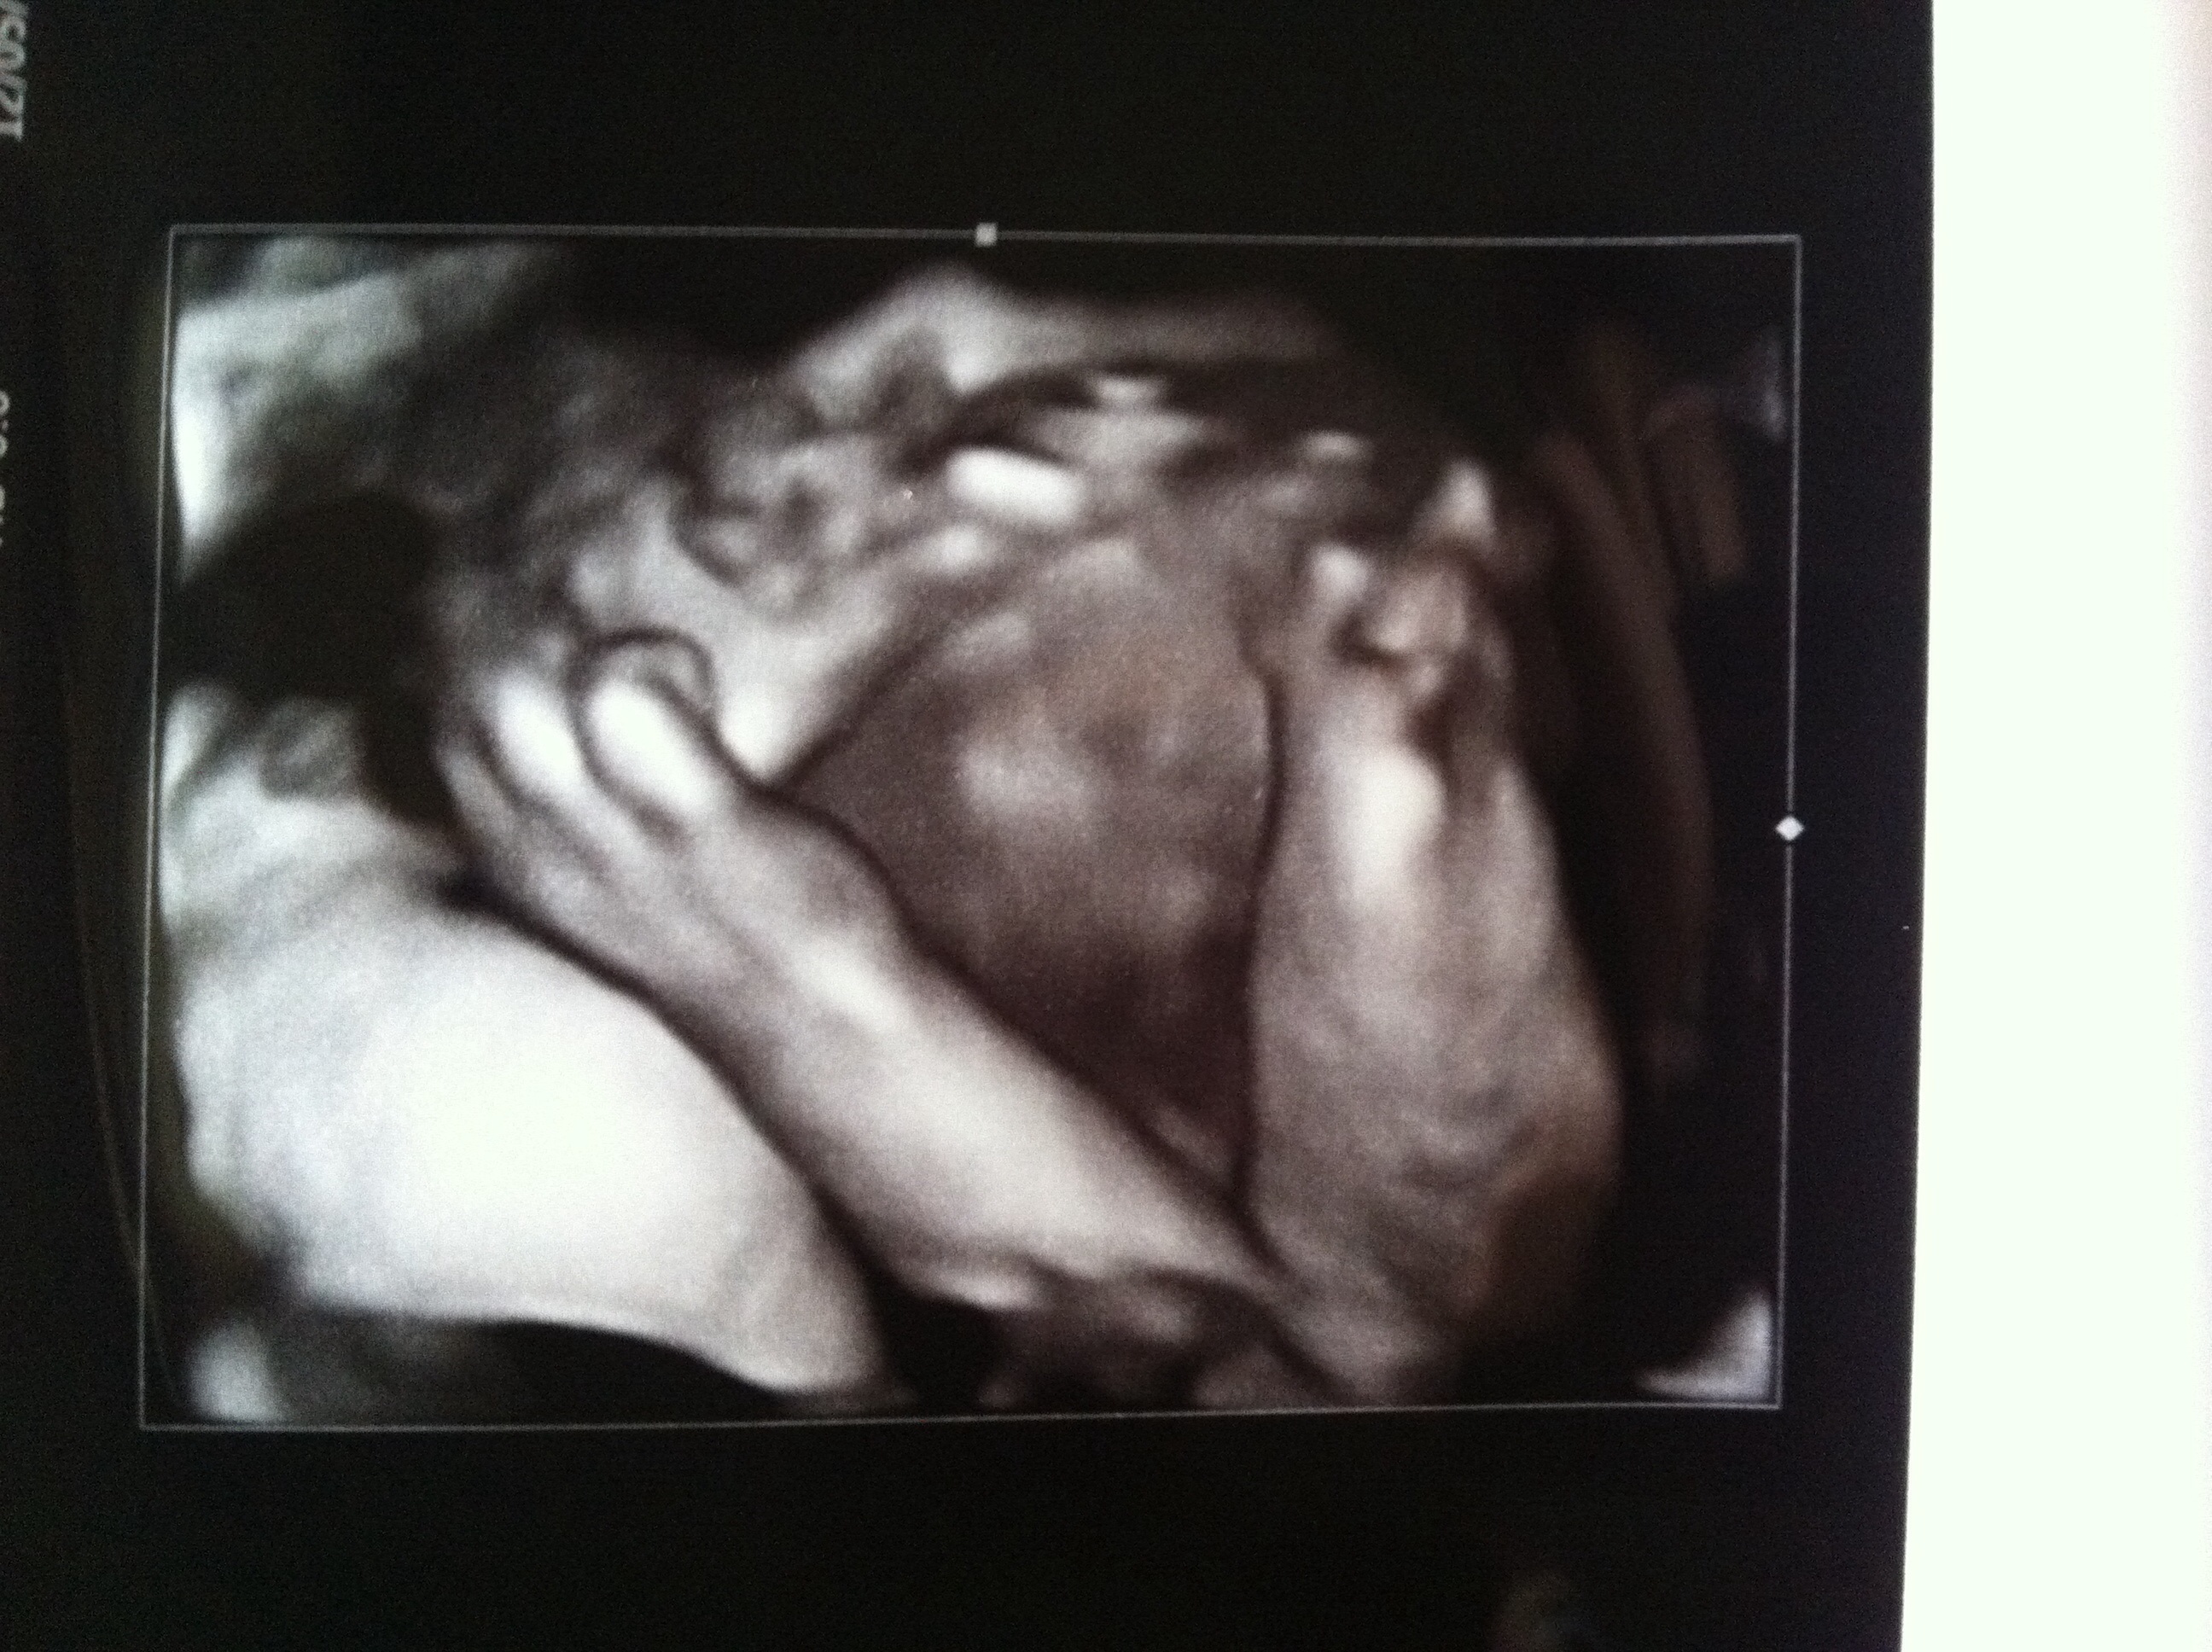

Just got back from my 28-wk sono, and it was worth the wait. The doc even did 3D to try to get me some good shots of S's face, but LO was feeling shy and hid in her arms. But she also put on a little show for us; she kept grabbing her foot, and the doc got a good pic of it. She's flipped so is head-down (yay), and her feet are where I thought they were: in my right side. She's been very kicky/pokey lately. Doc is concerned about her size and how it might be related to GD (my test is Monday). She's measuring as big as most LOs at 30 weeks at 3+lbs. DDs were absolutely perfect throughout the appt, to my huge relief. They seemed really fascinated by the whole sono process. All in all, it was an awesome appt.